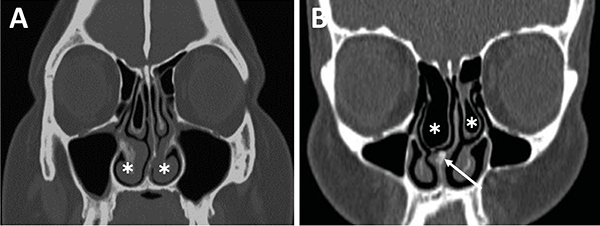

La principal utilización de la tomografía es la identificación de estructuras anatómicas óseas útiles a la hora de la planificación quirúrgica. Con una tomografía con reconstrucción 2D se pueden evidenciar con sencillas mediciones las siguientes características: septum nasal, variantes turbinales, presencia y posición de los ostiums esfenoidales, rostrum esfenoidal y su relación con el vómer, neumatización del seno esfenoidal, tabiques intrasinusales, distancia intercarotídea, grado de neumatización de etmoides posterior e identificación de nervios ópticos en su trayecto adyacente al seno esfenoidal.23,29

La evaluación del septum nasal podrá mostrar si presenta desviación o prominencias óseas que puedan dificultar el abordaje como también el tallado de un colgajo nasoseptal del lado elegido (fig. 9).[28] En caso de desvío septal se puede realizar septoplastia selectiva de la región desviada para logar un abordaje adecuado .

Figura 9: Desvío septal severo en TC cortes coronales. A) Inferior a fosa nasal derecha; B) Medio a fosa nasal izquierda.

Figura 10: Variantes turbinales en TC cortes coronales. A) Hipertrofia turbinal inferior (asteriscos blancos); B) Cornetes medios bullosos (asteriscos blancos) y desvío septal-espolón (flecha blanca).